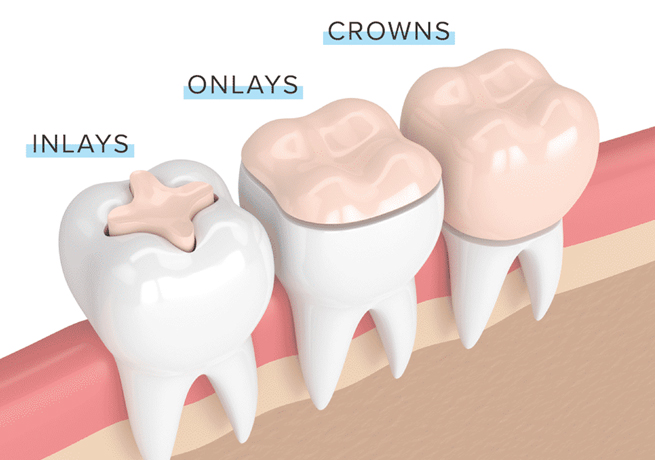

An Inlay/Onlay is a small restoration usually made of a very strong ceramic. When a large portion of a natural tooth is lost, the traditional method to replace the lost tooth structure is with a crown that covers the entire tooth in it’s entirety. However, with modern adhesive dentistry, we are able to manufacture much smaller restorations called inlays/onlays, and are thereby able to preserve much more of your tooth structure.

INLAY VS ONLAY – What’s the difference?

An onlay covers one or more “cusps” of your teeth – a cusp is the projection on teeth that help you chew your food. An inlay does not replace any cusps.